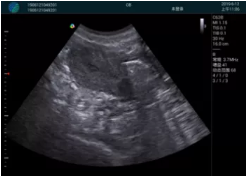

急診醫(yī)學(xué)的核心任務(wù)是對(duì)危重急的病人進(jìn)行快速診斷并進(jìn)行生命支持,在病人處理中的時(shí)效性和整體性顯得尤為重要。時(shí)效性是指要迅速及時(shí)的對(duì)病人的狀況作出初步診斷,同時(shí)采取相應(yīng)的有效措施,以挽救病人的生命。高效率的緊急救援,是政府機(jī)關(guān)、醫(yī)院對(duì)外形象展示的重要窗口,是衡量一個(gè)地區(qū)醫(yī)療技術(shù)及管理水平的重要標(biāo)志。為了適應(yīng)新時(shí)代急救系統(tǒng)的發(fā)展,新設(shè)備新技術(shù)在急救系統(tǒng)的應(yīng)用顯得越來越急迫??颠_(dá)i-M20便攜平板彩色超聲作為一種快速、無創(chuàng)的檢測(cè)設(shè)備在急救系統(tǒng)的應(yīng)用越來越普遍。